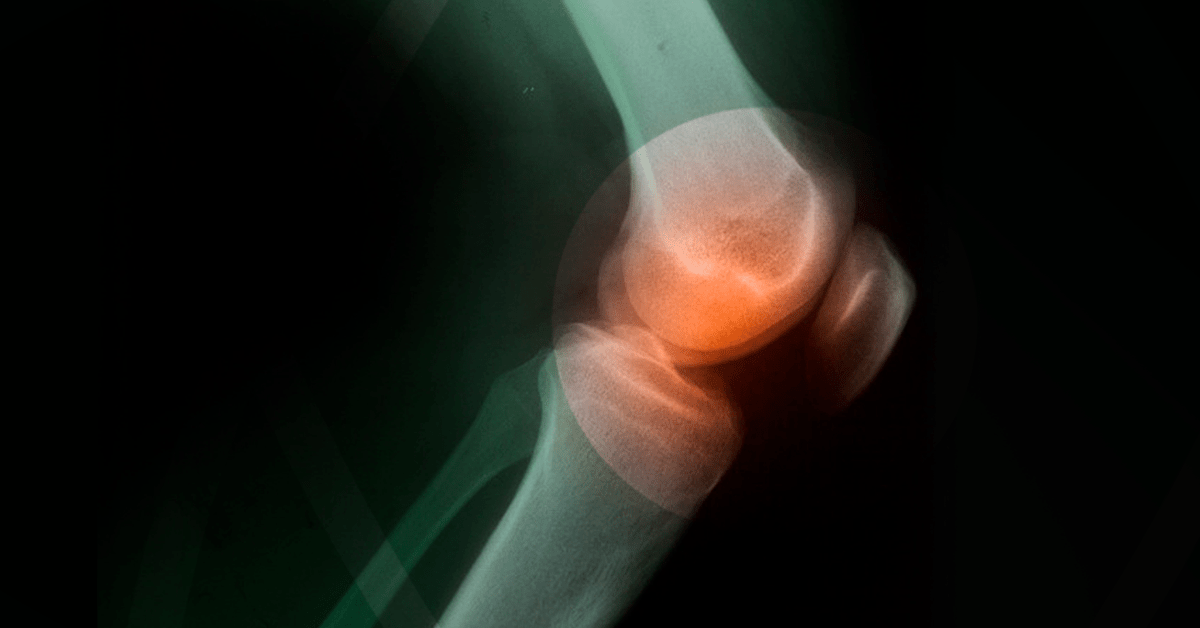

O diagnóstico decâncernosossosé feito pelo oncologista através da avaliação dossintomas, histórico de saúde e exames físico, laboratoriais e de imagem.

Ossintomasdocâncernosossosvariam conforme o tipo e a localização, mas há sinais que merecem atenção: Dor óssea persistente: é osintomamais comum, e tende a piorar à noite ou durante o repouso.

Quais são os primeiros sinais decâncernosossos? Ossintomasiniciais frequentemente incluem dor óssea persistente, inchaço ou sensibilidade perto do tumor, e, em alguns casos, uma massa palpável. A dor associada aocâncerósseo é constante ou intermitente?

Ocâncernosossosé um tumor maligno que se originarnopróprioossoou pode ser causado por metástase de outro tumor, provocandosintomascomo dornoosso, inchaço nas articulações e fraturas ósseas com pequenos traumas. Entenda o que écâncernosossos,sintomas, causas, tipos e

O que é, exatamente,câncernosossos? Quais ossintomasde tumor ósseo?Existem alguns tipos decâncernosossoscomsintomasparecidos, podendo haver enfraquecimento dosossos, dores intensas e fraturas fáceis.